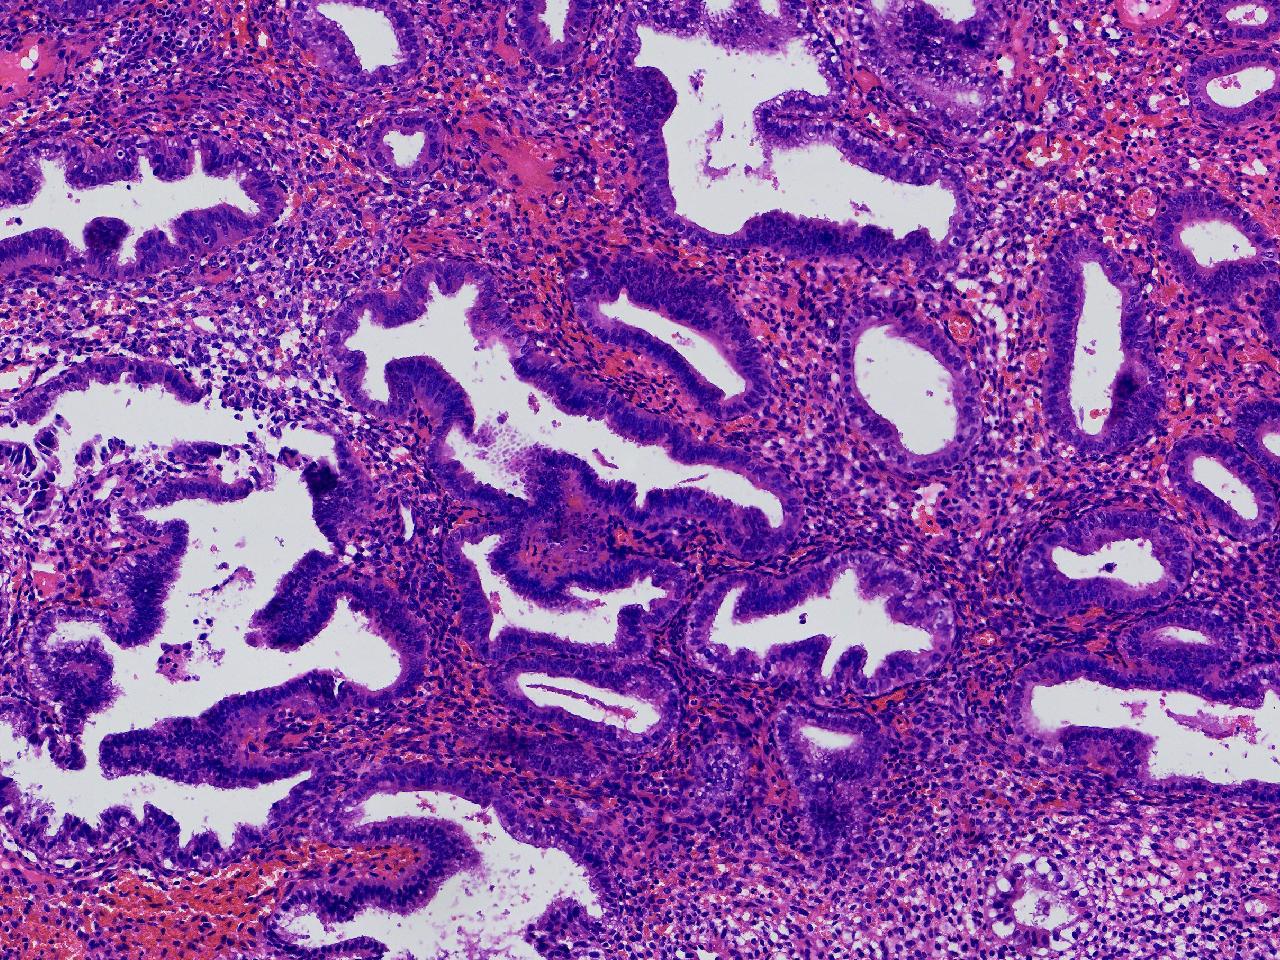

请教。1.有没有非典? 2.内膜是什么变化?

女,50岁,彩超示:粘膜厚度1.1cm。宫腔可见数个高回声,提示宫腔息肉。

子宫内膜+内膜息肉

灰粉色不整形软组织多块,3X3X2厘米。

子宫内膜息肉。

没有非典。

无非典型性子宫内膜增生,子宫内膜息肉

无非典内膜伴息肉。